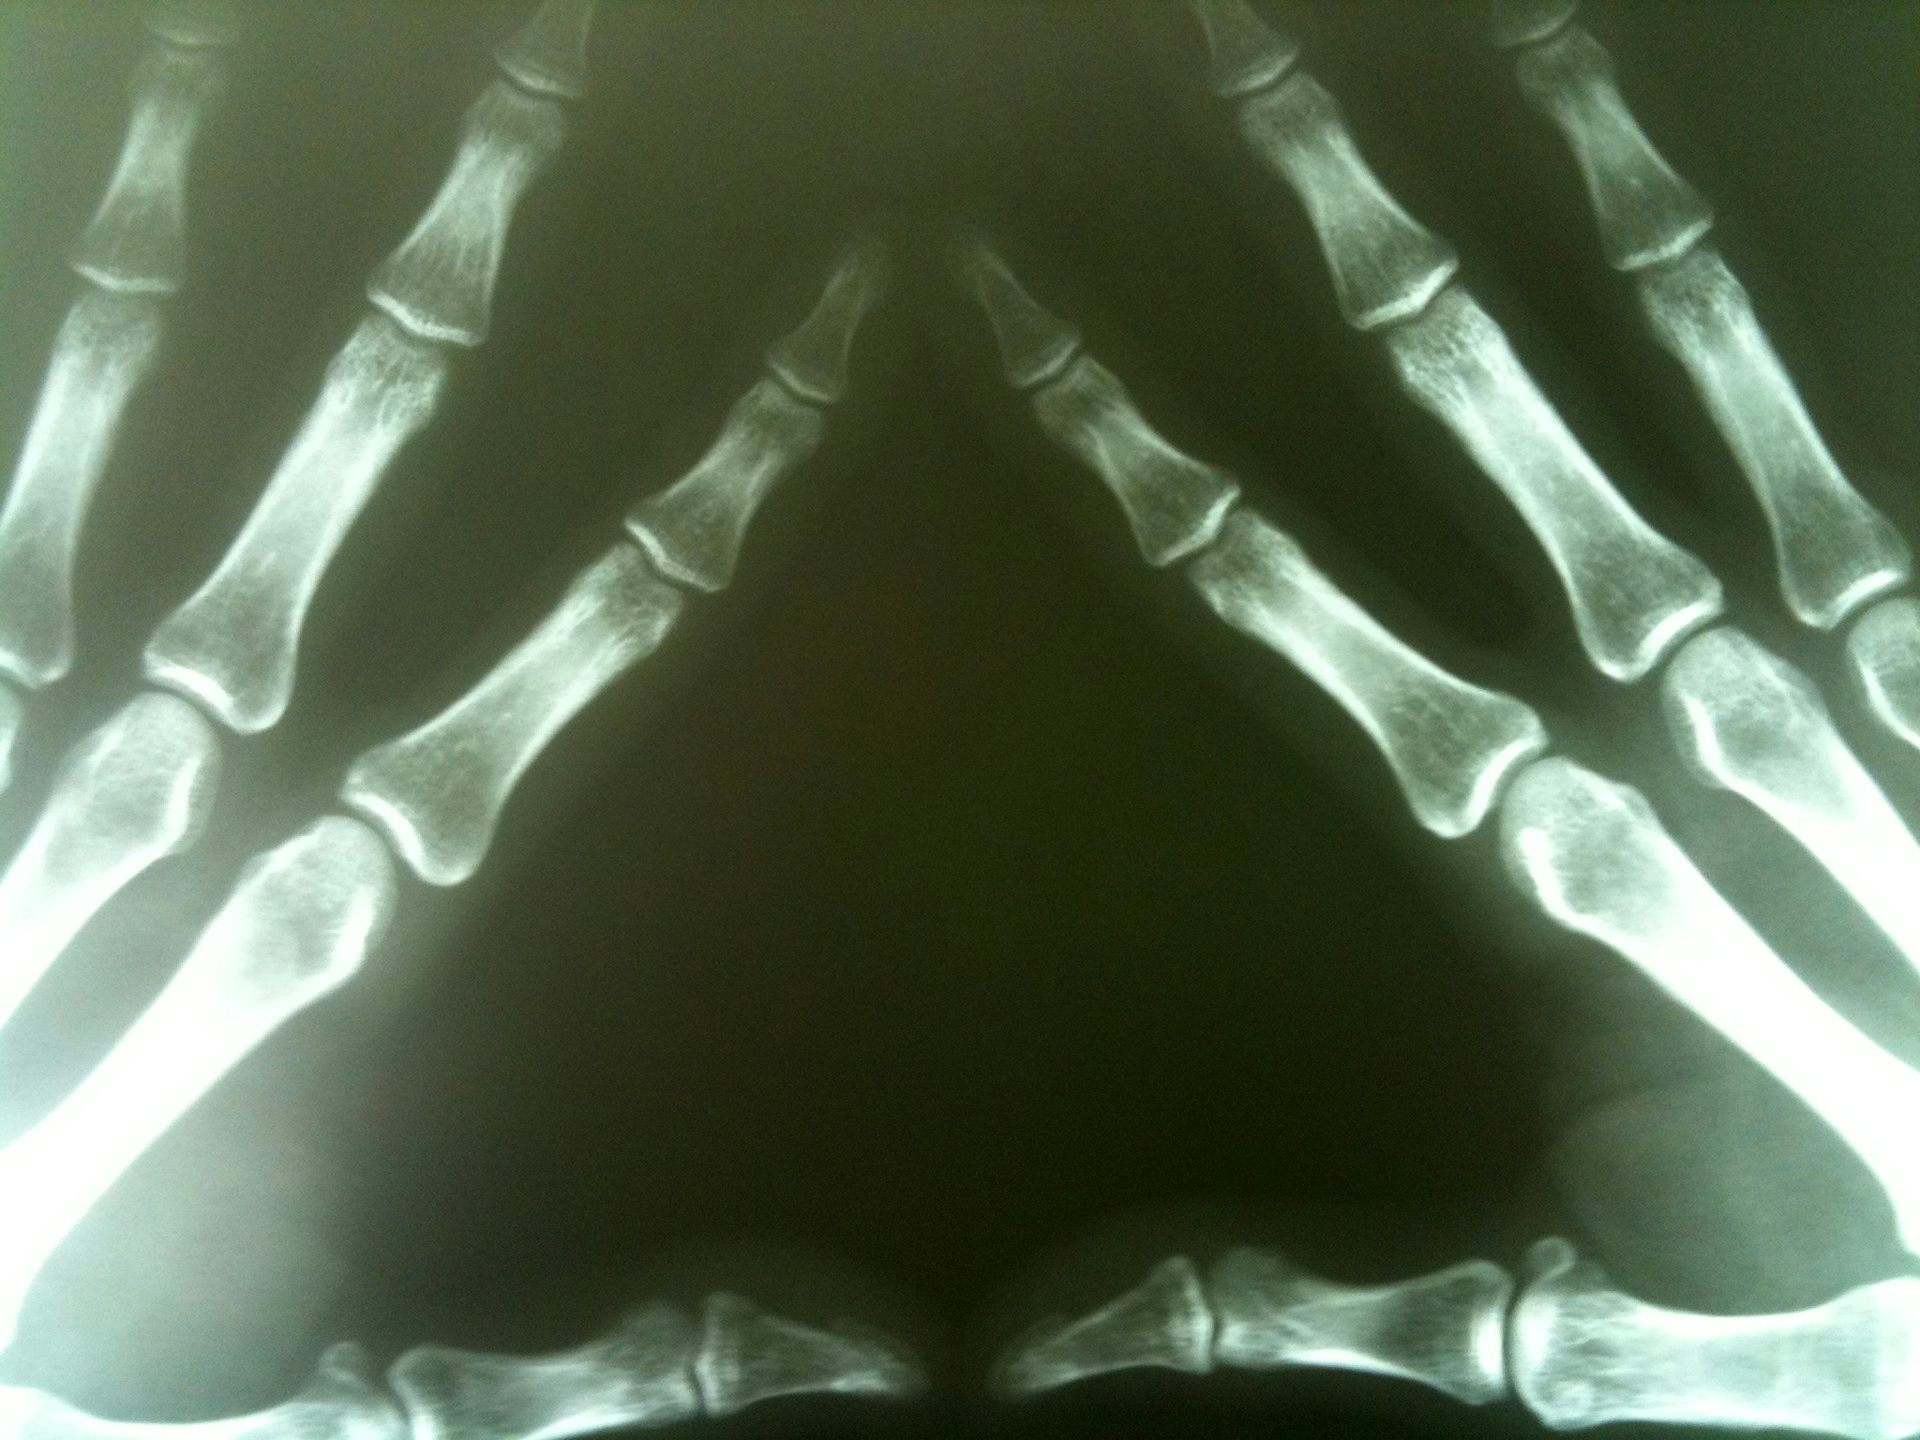

Физиотерапия костная мозоль на - фото презентация